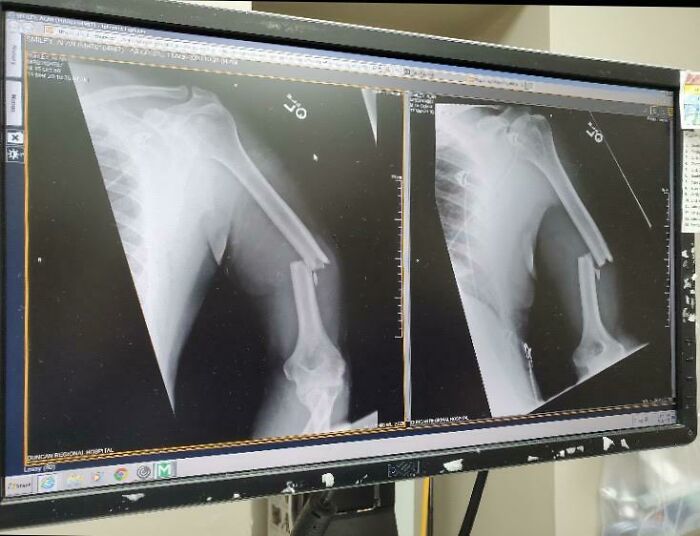

According To My Doctor I Was The First Person In The World To Receive A 3D Printed Bone In 2014. Without It, I Would Have Lost My Knee